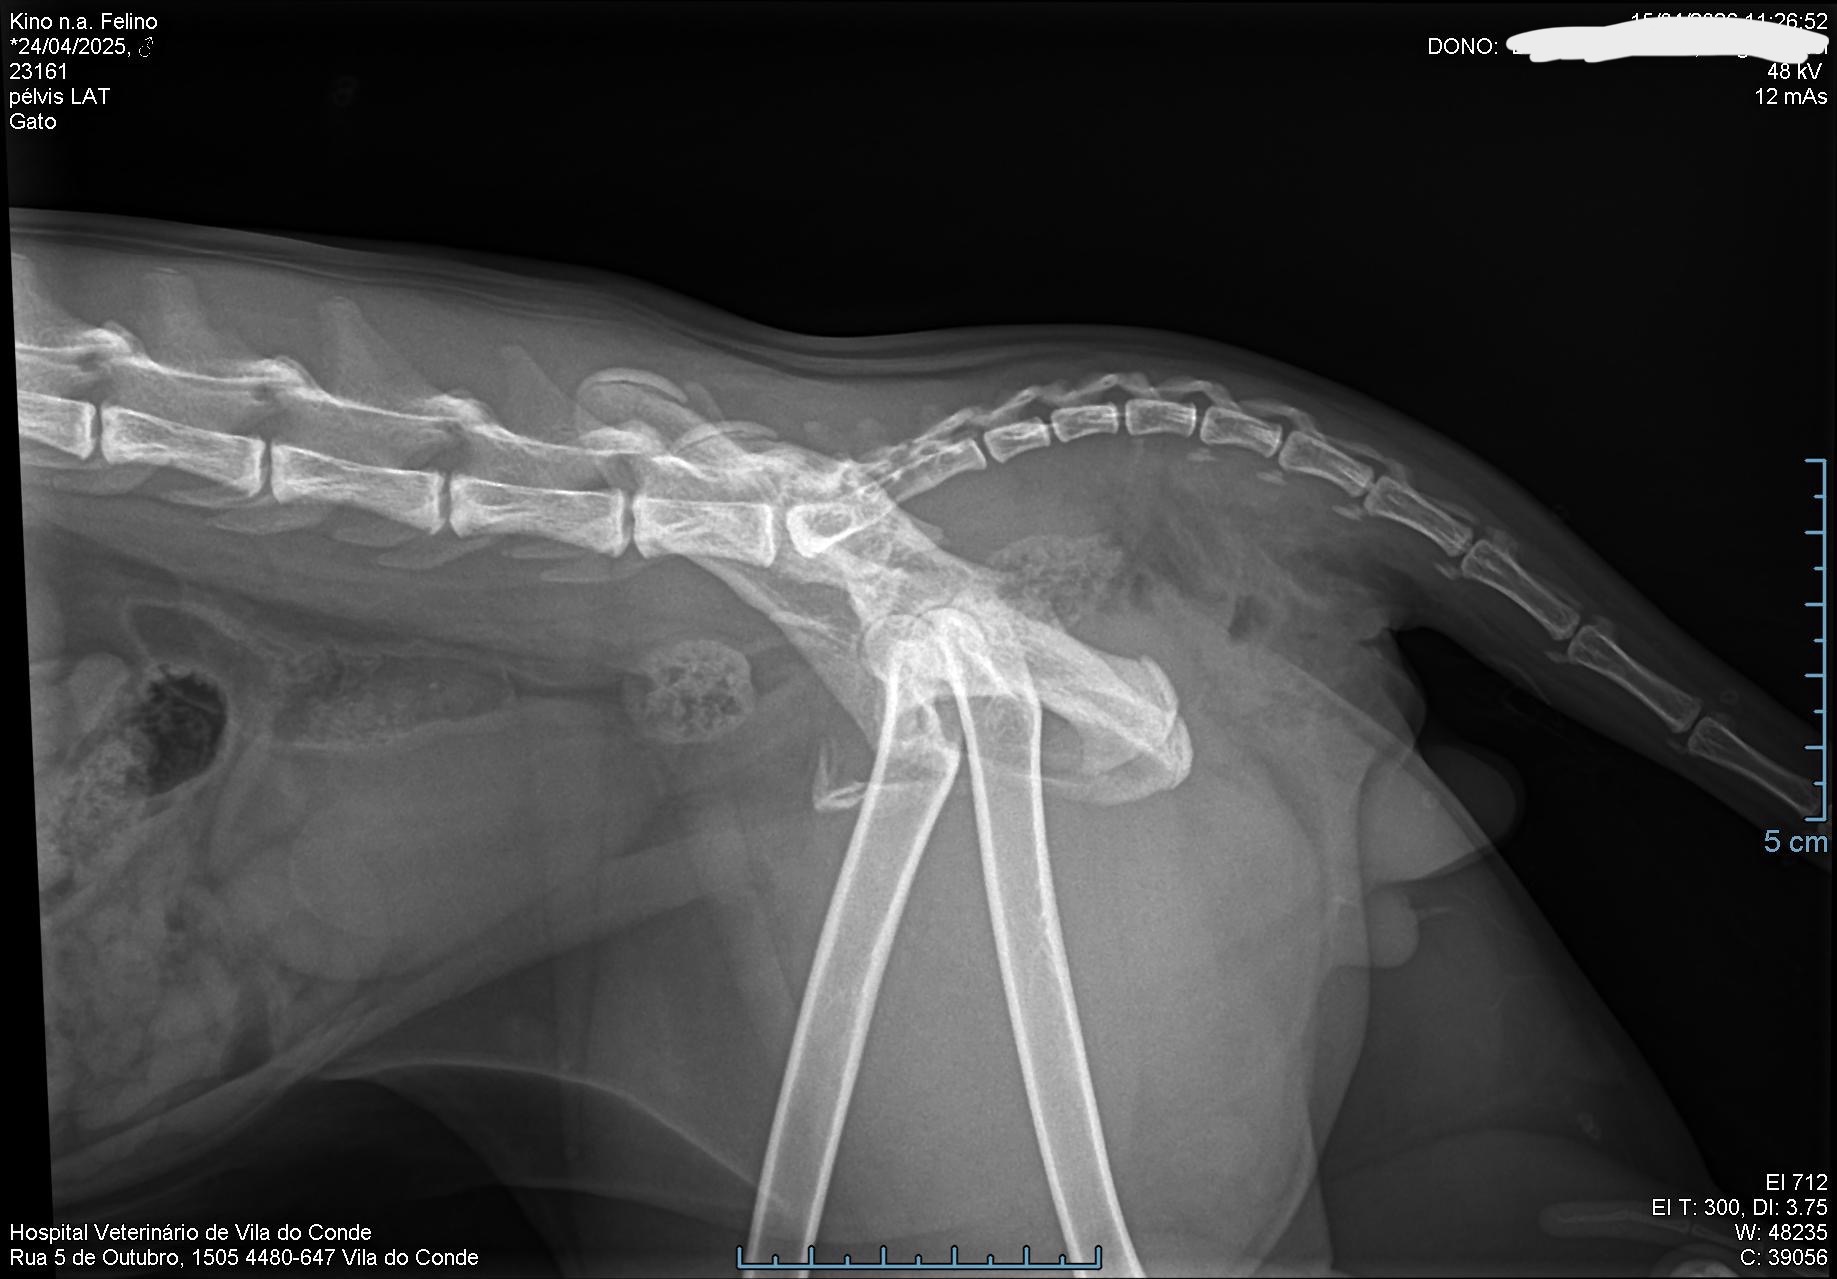

Hi everyone. You probably came from my post on r/cats. This is a fundraiser for Kino, my 1 year old cat who was hit by a car on 15/04 and will go through surgery on his hip. I shared a story of how our lives crossed paths, since being raised by his stray mom and how I helped her and the kittens.

There is also an alternative view of the x-ray.